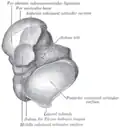

The body of the talus comprises most of the volume of the talus bone (ankle bone). It presents with five surfaces; a superior, inferior, medial, lateral and a posterior:[8]

- The superior surface of the body presents, behind, a smooth trochlear surface, the trochlea, for articulation with the tibia. The trochlea is broader in front than behind, convex from before backward, slightly concave from side to side: in front it is continuous with the upper surface of the neck of the bone.

- the inferior surface presents two articular areas, the posterior and middle calcaneal surfaces, separated from one another by a deep groove, the sulcus tali. The groove runs obliquely forward and lateralward, becoming gradually broader and deeper in front: in the articulated foot it lies above a similar groove upon the upper surface of the calcaneus, and forms, with it, a canal (sinus tarsi) filled up in the fresh state by the interosseous talocalcaneal ligament. The posterior calcaneal articular surface is large and of an oval or oblong form. It articulates with the corresponding facet on the upper surface of the calcaneus, and is deeply concave in the direction of its long axis which runs forward and lateralward at an angle of about 45° with the median plane of the body. The middle calcaneal articular surface is small, oval in form and slightly convex; it articulates with the upper surface of the sustentaculum tali of the calcaneus.

- The medial surface presents at its upper part a pear-shaped articular facet for the medial malleolus, continuous above with the trochlea; below the articular surface is a rough depression for the attachment of the deep portion of the deltoid ligament of the ankle-joint.

- The lateral surface carries a large triangular facet, concave from above downward, for articulation with the lateral malleolus; its anterior half is continuous above with the trochlea; and in front of it is a rough depression for the attachment of the anterior talofibular ligament. Between the posterior half of the lateral border of the trochlea and the posterior part of the base of the fibular articular surface is a triangular facet which comes into contact with the transverse inferior tibiofibular ligament during flexion of the ankle-joint; below the base of this facet is a groove which affords attachment to the posterior talofibular ligament.

- The posterior surface is narrow, and traversed by a groove running obliquely downward and medialward, and transmitting the tendon of the Flexor hallucis longus. Lateral to the groove is a prominent tubercle, the posterior process, to which the posterior talofibular ligament is attached; this process is sometimes separated from the rest of the talus, and is then known as the os trigonum. Medial to the groove is a second smaller tubercle.